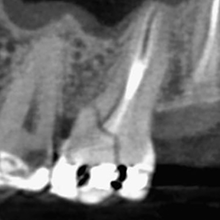

Imagem tomográfica do dente, evidenciando a fratura na mesio-palatina